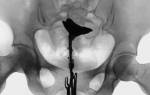

2. Непроходимость в маточных трубах.

Препарат Лонгидаза способен уменьшить или полностью устранить спайки в малом тазу